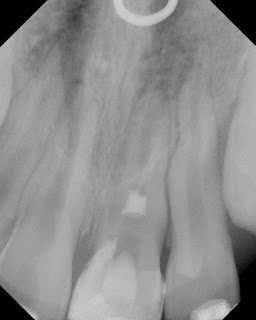

Pulpal regeneration allows “pulp-like” tissue to re-grow into the immature root and continue the development of the root. This provides the root with stronger, thicker root walls. Here’s another successful case of pulpal regeneration.

Pulpal regeneration was started. Complete pulpectomy was performed with minimal instrumentation to the apex, and irrigation with 5.25% NaOCl. A blood clot was initiated into the canal, a collagen plug was placed and an (white) MTA coronal barrier was placed below the level of the CEJ.